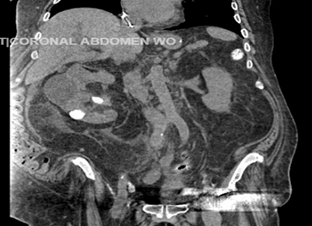

Figure 1. Computed tomography of the abdomen and pelvis with oral contrast.

Showing multiple cystic and solid appearing areas, dense

calcifications in the inferior aspect.

was done, computed tomography (ct) of the abdomen and pelvis without

intravenous contrast due to the impaired renal function, showed abnormal

appearing right kidney, with multiple cystic and dense appearing regions

measuring 17 cm in length, with retroperitoneal, enlarged lymph nodes adjacent

to the ivc up to 3 cm.